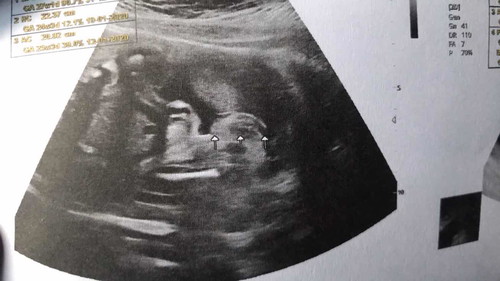

แม่ๆช่วยดูหน่อยค่ะ ซาวครั้งเเรกหมอบอกได้ ผญ ครั้งที่สอง ไม่เเน่ใจ ช่วยดูหน่อยค่ะ

ดูไม่ออกเลยค่ะ